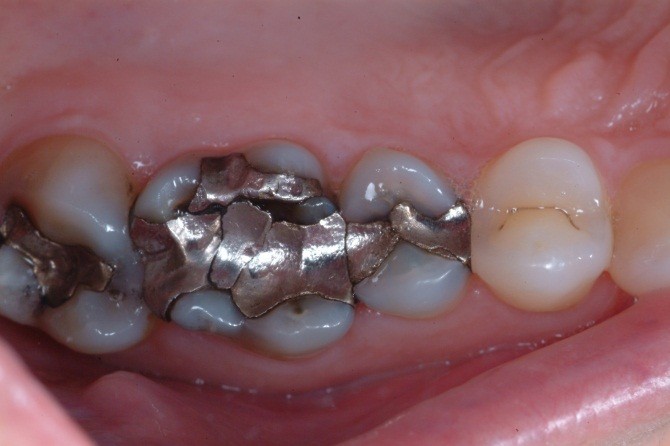

A toothache caused by a broken tooth (tooth fracture) without associated cavity or advanced gum disease. Biting on the area of tooth fracture can cause severe sharp pains. These fractures are usually due to chewing or biting hard objects such as hard candies, pencils, nuts, etc. Sometimes, the fracture can be seen by painting a special dye on the cracked tooth. Treatment usually is to protect the tooth with a crown. However, if placing a crown does not relieve pain symptoms, a root canal procedure may be necessary.